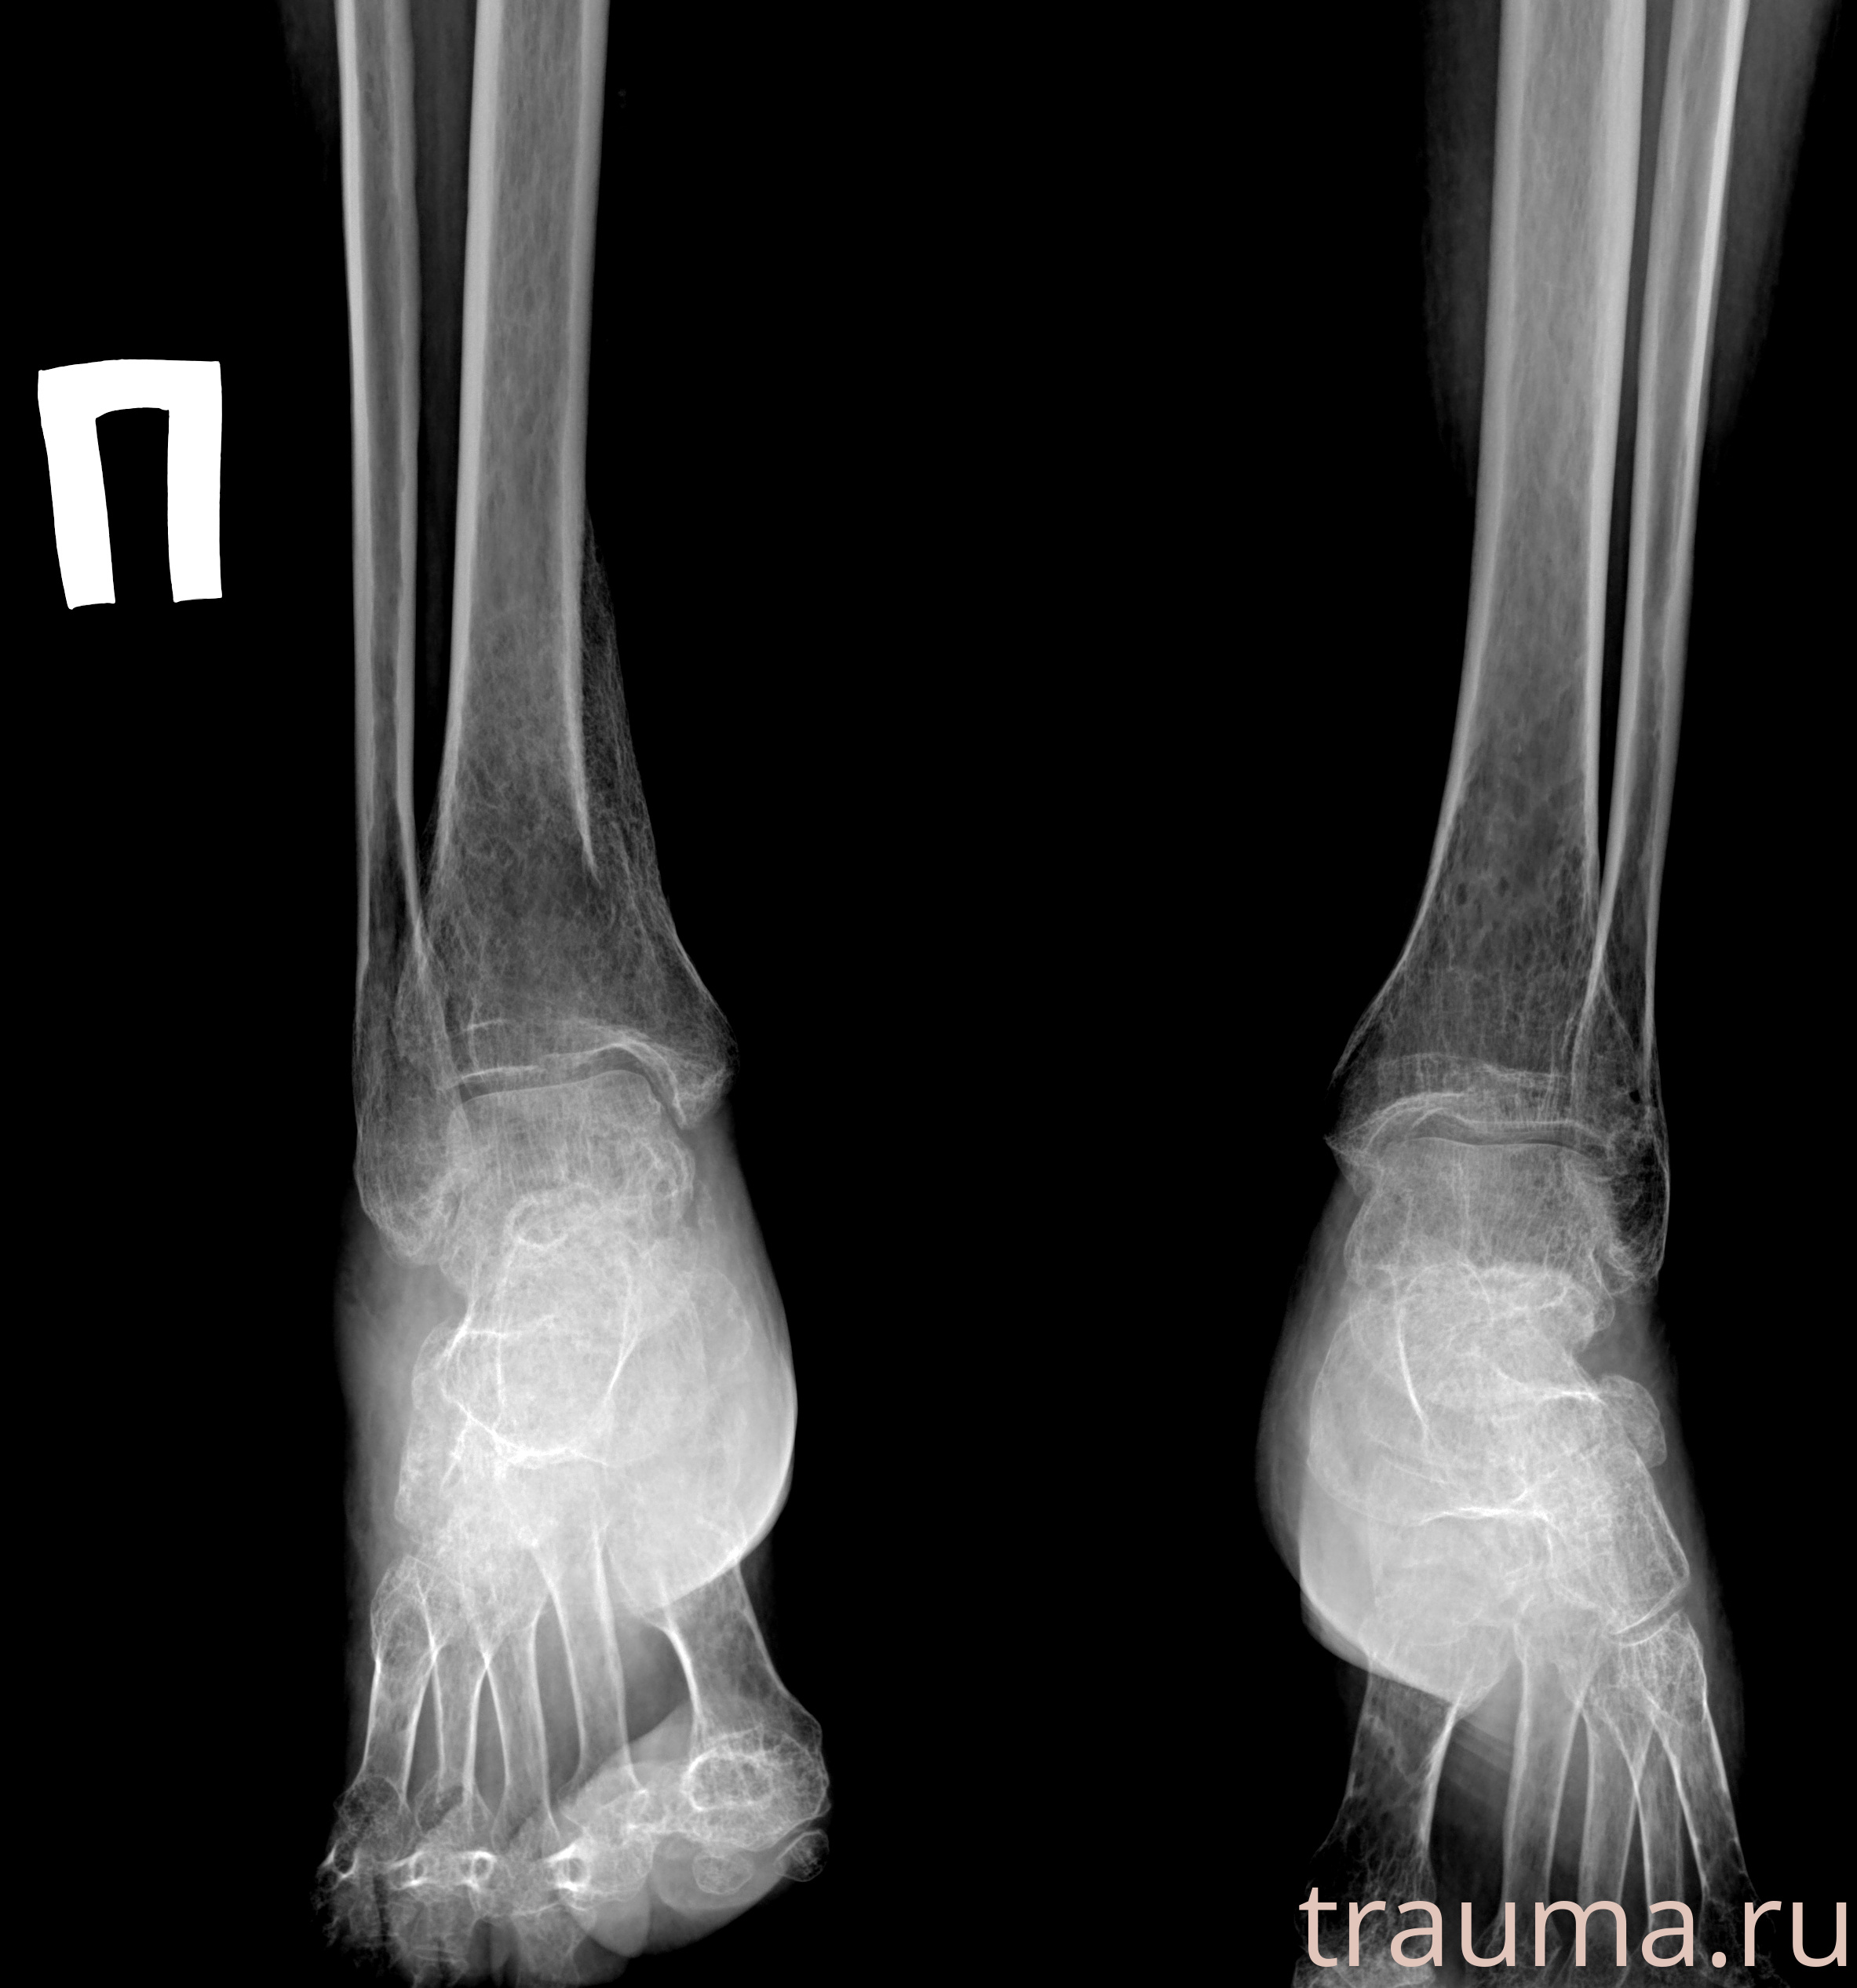

Рентгенограммы

Рентген на дому: по вашему адресу приезжает врач-рентгенолог, травматолог-ортопед с мобильным рентгеновским аппаратом, проводит диагностику травмы или заболевания, делает необходимые рентгенограммы, дает рекомендации по дальнейшему лечению. Получить качественные снимки в домашних условиях возможно благодаря уникальной методике, разработанной МосРентген Центром для института  Склифосовского